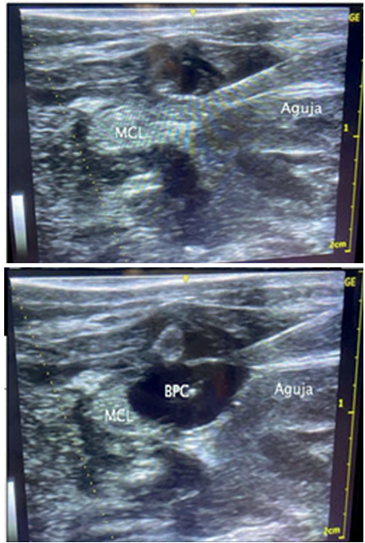

Uno de los aspectos diferenciales del protocolo desarrollado incluye la sedación y analgesia abarcando los períodos preoperatorio, intraoperatorio y posoperatorio (mediato e inmediato). El equipo de anestesiología del CHPR realizó una estrategia basada en la anestesia intravenosa total (TIVA, por su sigla en inglés) utilizando dexmedetomidina, propofol y remifentanil, administrados con bomba de infusión y evitando la utilización de paralizantes musculares. Formando parte del concepto de anestesia multimodal, en el período de aplicación del protocolo asistencial referido se logró sistematizar la realización de anestesia locorregional (en 10/18 pacientes versus 3/29 pacientes en el período previo). El objetivo planteado fue reducir al mínimo el uso de agentes anestésicos intraoperatorios, que pueden prolongar el efecto anestésico en el posoperatorio. En este procedimiento el fármaco utilizado (bupivacaína 0,25%) se administró a nivel de las fascias del músculo cuadrado lumbar, difundiendo hasta el espacio paravertebral, determinando bloqueo analgésico de la pared y de la cavidad abdominal. La analgesia regional mediante BCL ha sido bien descripta en adultos, sin embargo, en pacientes pediátricos con cirugía abdominal, la evidencia disponible es aún escasa, aunque en los estudios realizados ha mostrado efectividad en lograr analgesia sostenida en el posoperatorio. La dosis utilizada (0,3-0,5 ml/kg de bupivacaína al 0,25%) surge de la adaptación de los estudios realizados en niños, considerando las características propias del período neonatal, sobre todo la menor proporción de proteínas plasmáticas a los que se une el fármaco, así como el menor metabolismo y clearence hepático. Si bien no se constataron eventos adversos vinculados a la estrategia analgésica empleada, claramente este reporte no está diseñado con ese objetivo y es motivo de un estudio particular cuyos resultados serán presentados aparte (Figura 3).

Figura 3 Analgesia locorregional. Administración de bupivacaína mediante inyección (aguja) en la fascia a nivel del músculo cuadrado lumbar. En la imagen A se observa la aguja penetrando en la fascia y en la imagen B el líquido desplazándolo (espacio negro).